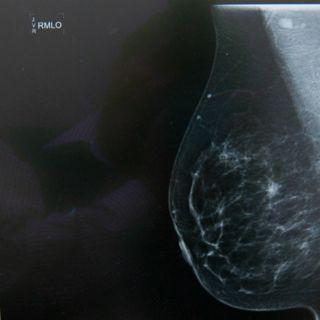

CIUDAD DE MÉXICO (06/ENE/2016).- La Universidad Autónoma de San Luis Potosí (UASLP) estudia diversas técnicas para mejorar el análisis de imágenes médicas, pues la imagenología clínica permite explorar a detalle las principales funciones del cuerpo.

La alumna de la Facultad de Ciencias, Sarahí Hernández Juárez, trabaja para realizar comparaciones cuantitativas de métodos de segmentación de imágenes médicas, para lograr organizar distintos tipos de estructuras del cuerpo.

"El objetivo inicial del proyecto era comparar métodos de segmentación en el ámbito clínico para lograr segmentar distintos tipos de estructuras de interés", dijo Hernández en una entrevista con la Agencia Informativa del Consejo Nacional de Ciencia y Tecnología ( Conacyt).

"Después se complementó con la comparación por parte de un experto clínico, para verificar la eficiencia de los métodos de segmentación conocidos, en este caso enfocado en el tratamiento de radioterapia", añadió.

Los métodos que se aplicaron fueron K-means, Otsu y Chan-Vese para la segmentación de imágenes de pulmones y un tumor cerebral.

El análisis cuantitativo constó del cálculo de índices de precisión que comparan la segmentación obtenida por cada método con otra de forma tradicional por un especialista clínico.

Los índices adquiridos fueron la distancia simétrica media, la distancia máxima, el porcentaje de distancias mayores a la dimensión del pixel y el índice de superposición.

Los resultados arrojaron que para la segmentación de los pulmones los algoritmos se comportan de manera similar, pero en el caso del tumor, el método de Chan-Vese es preferible.